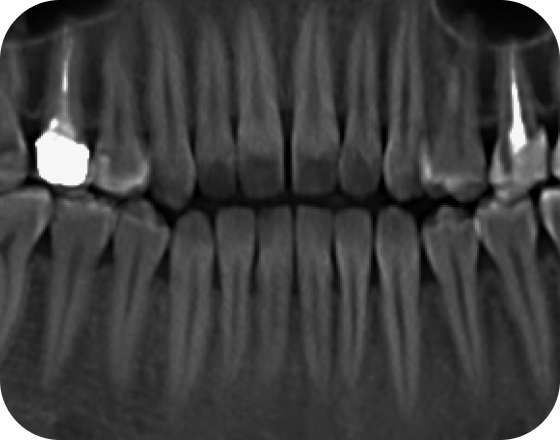

Нужно ли удалять зубы мудрости?

В 95% случаев мы рекомендуем удалить все 4 зуба мудрости, так как они могут мешать перемещению зубов или искривить зубы после лечения

В редких случаях их можно не удалять. Требуется консультация специалиста

Нужно ли удалять зубы мудрости